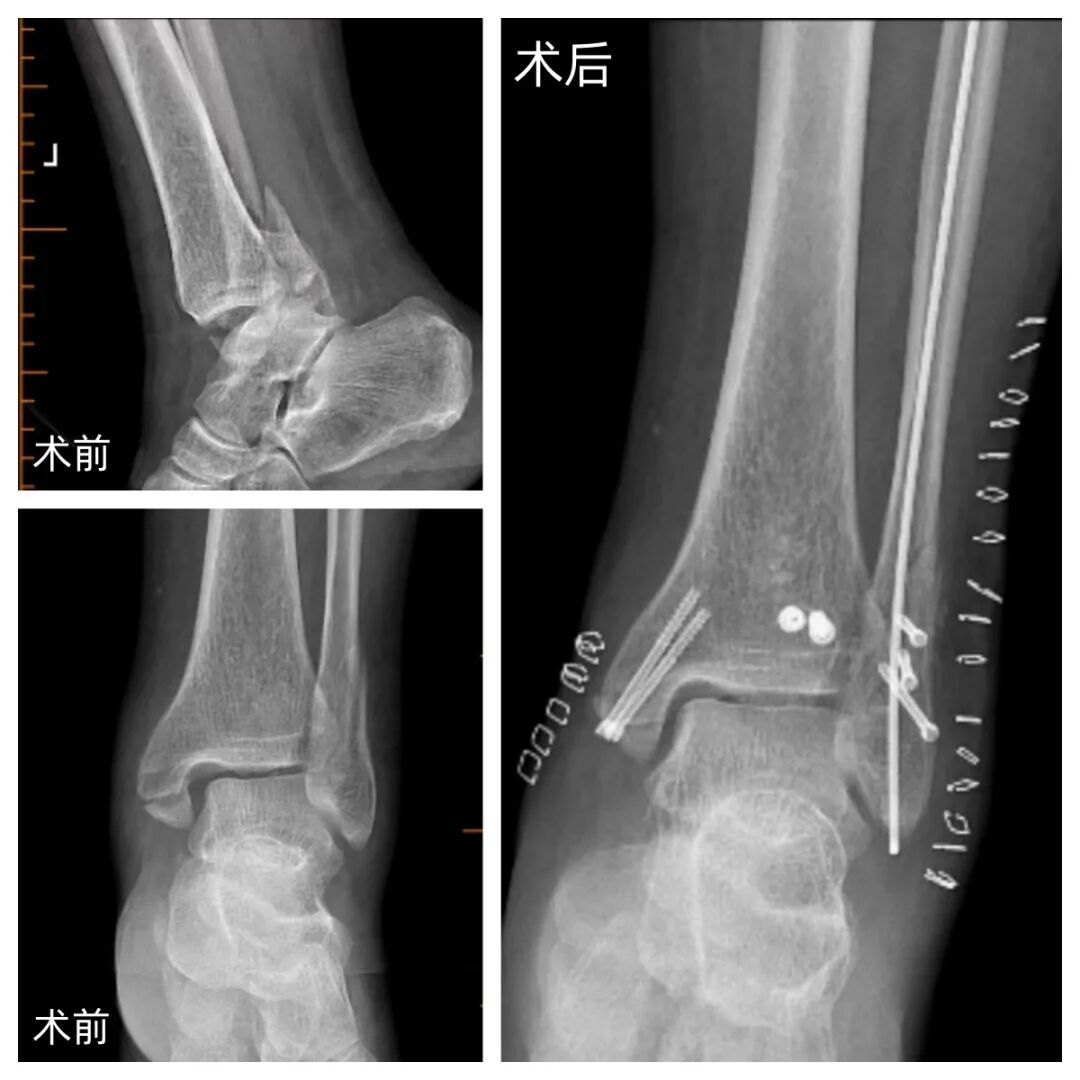

近年来,河南大学淮河医院创伤骨科郭建阔主任团队在临床开展弹性髓内针联合 Herbert 螺钉治疗外踝骨折的改良术式,截至目前已完成三十余例,取得了满意的临床效果。

针对上述问题,我院郭建阔主任团队采用弹性髓内针纵向髓内固定联合 Herbert 螺钉固定骨折断端的改良术式。该术式旨在最大限度恢复踝关节解剖结构与维持关节面平整,同时减少传统切开复位对软组织的干扰,为外踝骨折的手术固定提供了一种新的选择。

弹性髓内钉属于中心性内固定器械,其直径较细,术中无需扩髓,配合 Herbert 螺钉对骨折断端进行固定,有助于防止骨折旋转和成角移位,更好地稳定骨折断端,缓解局部疼痛,促进骨折愈合,并有利于术后踝关节活动度的恢复。由于该术式对皮肤软组织破坏较小,尤其对于开放性或闭合性软组织损伤明显的不稳定型踝关节骨折脱位,显示出良好的临床应用前景。